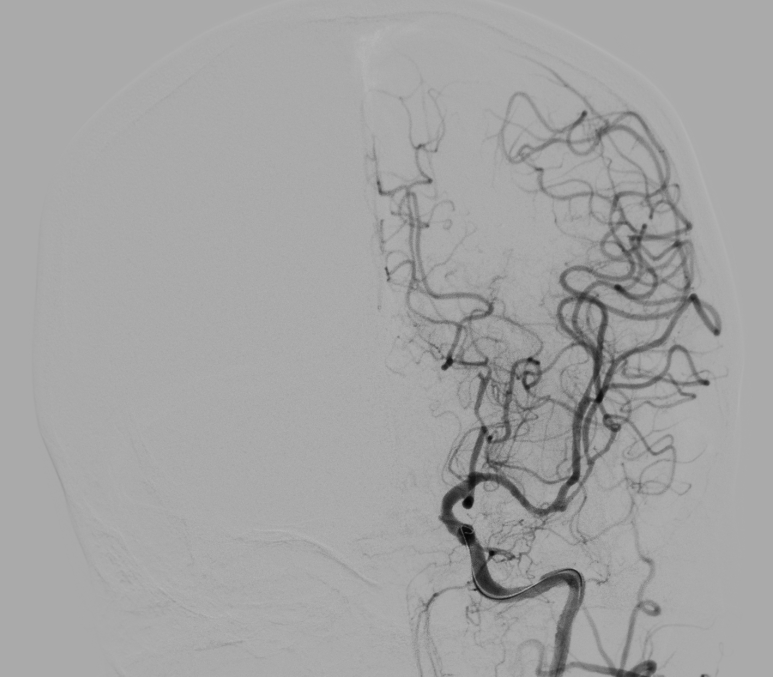

5 分钟后,张女士被推进介入手术室,急诊脑血管造影进一步确认了血管闭塞情况。

10 分钟后,手术顺利完成,堵塞血管成功开通,濒临坏死的脑细胞被及时 “救回”,张女士的病情得到了有效控制。

而取栓手术,就是医生通过微创的方式,直接把堵在血管里的血栓取出来,快速打通被堵塞的 “生命河道”,拯救濒临死亡的脑细胞。